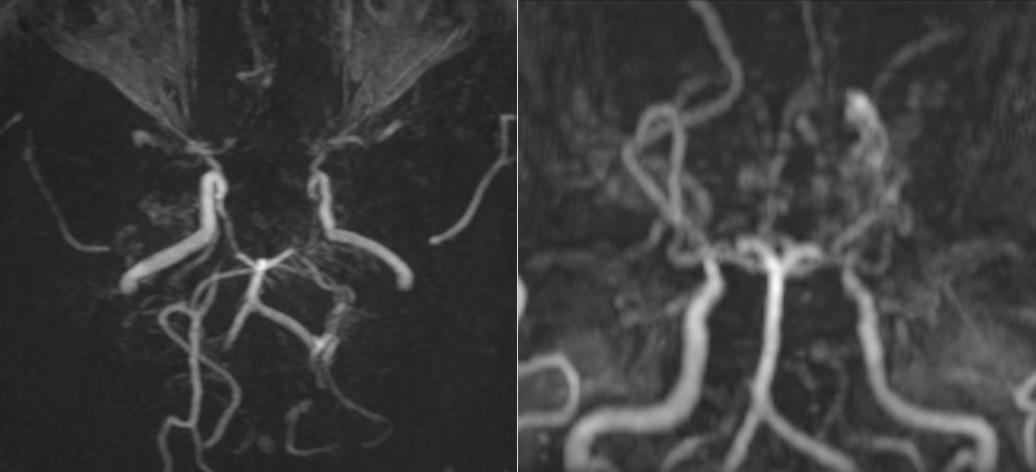

Các mạch máu não của bệnh nhân nhìn như “làn khói thuốc lá” trên phim chụp MRI.

Tại Bệnh viện đa khoa Medlatec, qua thăm khám lâm sàng, bệnh nhân không có dấu hiệu thần kinh khu trú hay tăng áp lực nội sọ. Để làm rõ nguyên nhân, bác sĩ chỉ định chụp cộng hưởng từ (MRI) sọ não. Kết quả MRI cho thấy, hình ảnh tổn thương hẹp tắc động mạch cảnh trong hai bên và các nhánh của đa giác Willis, xung quanh hình thành tuần hoàn bàng hệ với nhiều mạch máu nhỏ bất thường.

Đồng thời, trên chuỗi xung FLAIR, xuất hiện những dải tín hiệu sáng chạy dọc theo rãnh cuộn não, gợi hình ảnh “dây thường xuân” len lỏi trên bề mặt, phản ánh sự gia tăng tuần hoàn bàng hệ màng mềm để bù đắp cho tình trạng thiếu máu não do tắc nhánh mạch não. Bên cạnh đó, bác sĩ cũng phát hiện một hình ảnh tổn thương cũ ở vùng trán trái, là biến chứng của bệnh lý Moyamoya.

Chẩn đoán hình ảnh phát hiện tình trạng hẹp hoặc tắc nghẽn phần cuối của động mạch cảnh trong sọ, rồi lan rộng ra các động mạch não trước, não giữa, não sau; phát hiện mạng lưới mạch máu bất thường ở vùng lân cận của các tổn thương dạng “làn khói thuốc”. Bệnh Moyamoya nếu không được phát hiện và điều trị kịp thời có thể dẫn đến đột quỵ, tàn phế hoặc tử vong.

Moyamoya trong tiếng Nhật Bản là “làn khói thuốc lá”, mô tả tuần hoàn bàng hệ là mạch máu nhỏ bất thường.